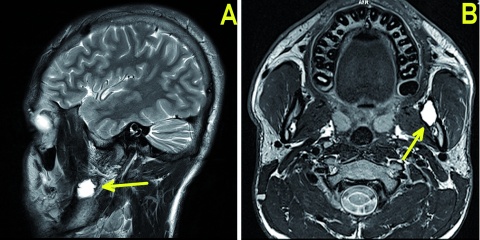

MehrFlugmedizin und Zahngesundheit: Juvenile Knochenzyste in der Mandibula bei einem Jetpiloten-Anwärter – Fallbericht

Claudia Lorenz Zentrum für Luft- und Raumfahrtmedizin der Luftwaffe, Fachgruppe II3 – Klinische Flugmedizin, Fürstenfeldbruck